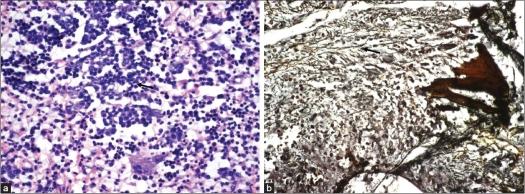

Extramedullary hemopoiesis (EMH) is a common compensatory phenomenon associated with chronic hemolytic anemia. Abnormal hemopoietic tissue usually develops in sites responsible for fetal hemopoiesis, such as spleen, liver and kidney; however, other regions such as the spine may also become involved. In this study, a patient presenting with spastic paraparesis due to EMH in the dorsal spine is described. A 62-year-old man presented with paraparesis. Magnetic resonance imaging revealed a large lesion involving the T2-L2 vertebral levels with a large extradural component causing thecal sac compression. Laminectomy with excision of mass was carried out. The histopathology revealed EMH. The patient had no known cause for EMH at the time of diagnosis but, subsequently, a bone marrow examination revealed early myelofibrosis. This case represents the rare occurrence of a large extradural extramedullary hematopoiesis in a patient with no known predisposing factor for hemopoiesis at the time of presentation.

髓外造血(EMH)是一种与慢性溶血性贫血相关的常见代偿现象。异常造血组织通常在负责胎儿造血的部位发展,如脾脏、肝脏和肾脏;然而,其他区域如脊柱也可能受累。在本研究中,描述了一名因胸椎髓外造血导致痉挛性截瘫的患者。一名62岁男性出现截瘫。磁共振成像显示一个大的病变累及T2-L2椎体水平,有一个大的硬膜外成分导致硬膜囊受压。进行了椎板切除术并切除肿块。组织病理学显示为髓外造血。该患者在诊断时没有已知的髓外造血病因,但随后骨髓检查显示早期骨髓纤维化。该病例代表了一例罕见的在就诊时无已知造血易感因素的患者出现大型硬膜外髓外造血的情况。